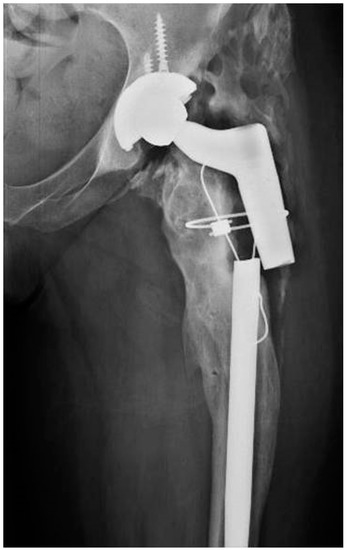

2.1. Case 1